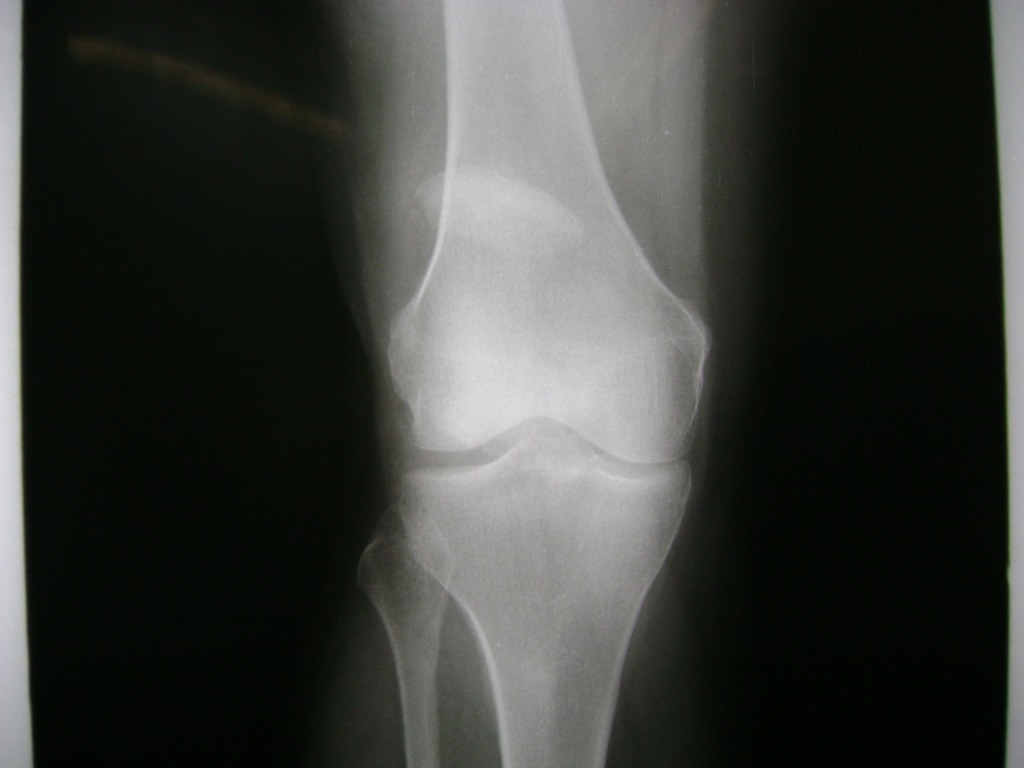

Cirugía de Fémur - Rodilla

La artroscopia de rodilla es un cirugía en el cual la estructura interna de la articulación es examinada ya sea para realizar un diagnostico o para realizar un tratamiento, este procedimiento se realiza utilizando un instrumento parecido a un pequeño tubo llamado artroscopio.